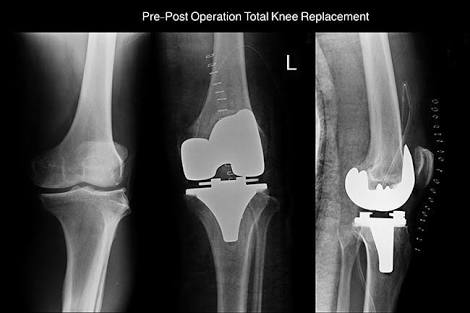

四期患者:4期的骨关节炎患者关节已经出现了严重的畸形,这个时期患者会非常的痛苦,关节会有严重的畸形,通常不能行走很长的距离,有一些患者甚至行走500米就疼痛难忍了。而且患者通常会出现比较明显的休息痛以及静息痛,什么意思呢?就是说,不动也痛。

此时我们只有通过进行关节置换手术的办法,才能帮助患者来解决痛苦。医生也知道很多患者不想做全膝关节置换术,所以说现在也研究出来单髁的置换手术,也算是一种保膝治疗。